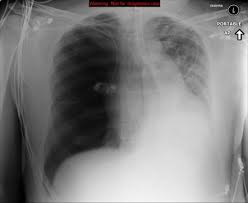

X Ray Rounds Plain Chest Radiographs Ppt Video Online Download

X Ray Rounds Plain Chest Radiographs Ppt Video Online Download from slideplayer.com